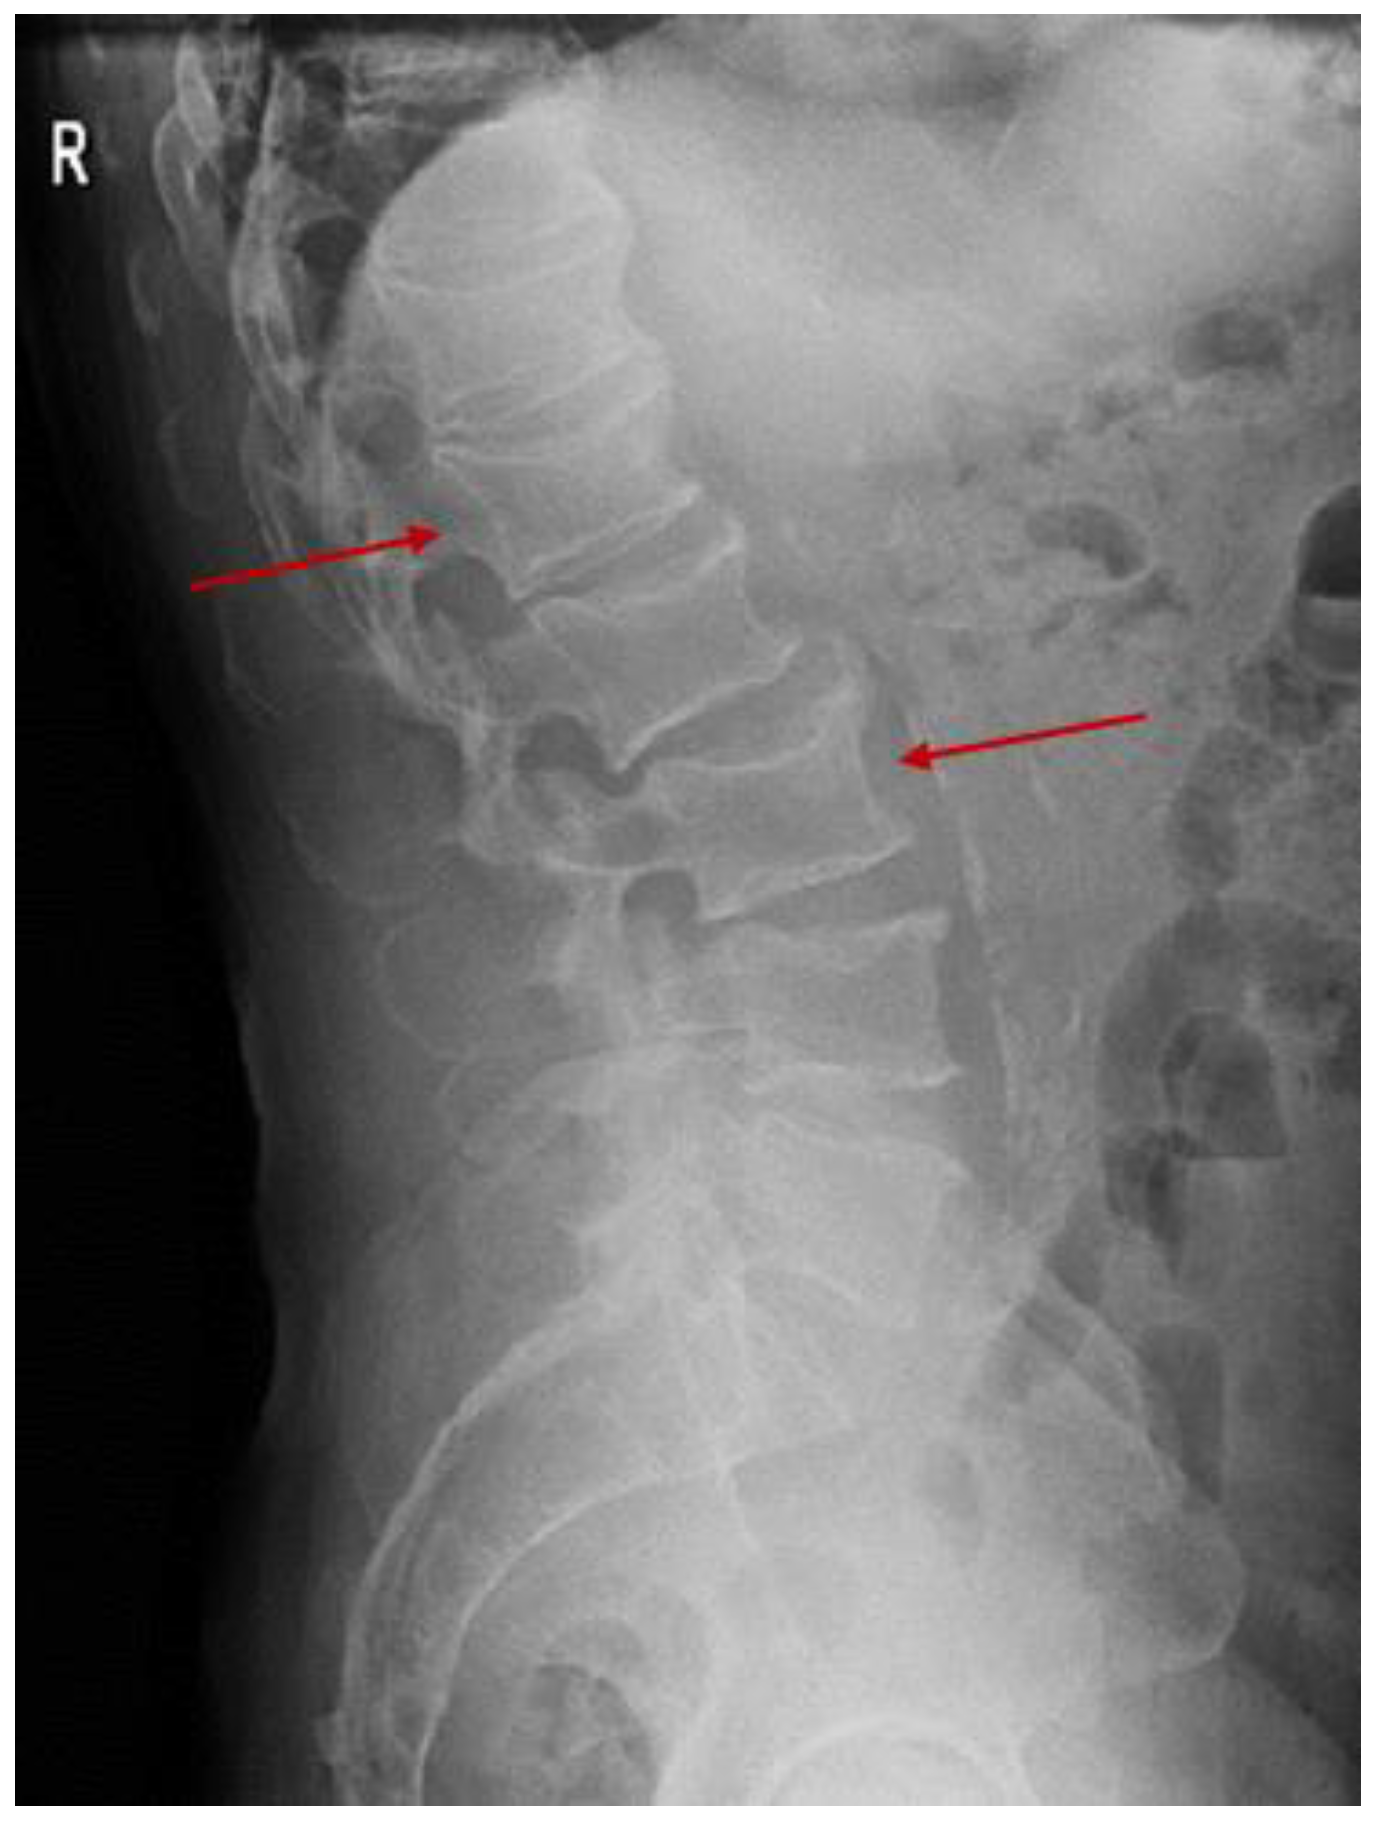

3.2.1. A Fine Index of Clinical Suspicion: Low Back Pain

3.2.2. Additional Imaging Assessments